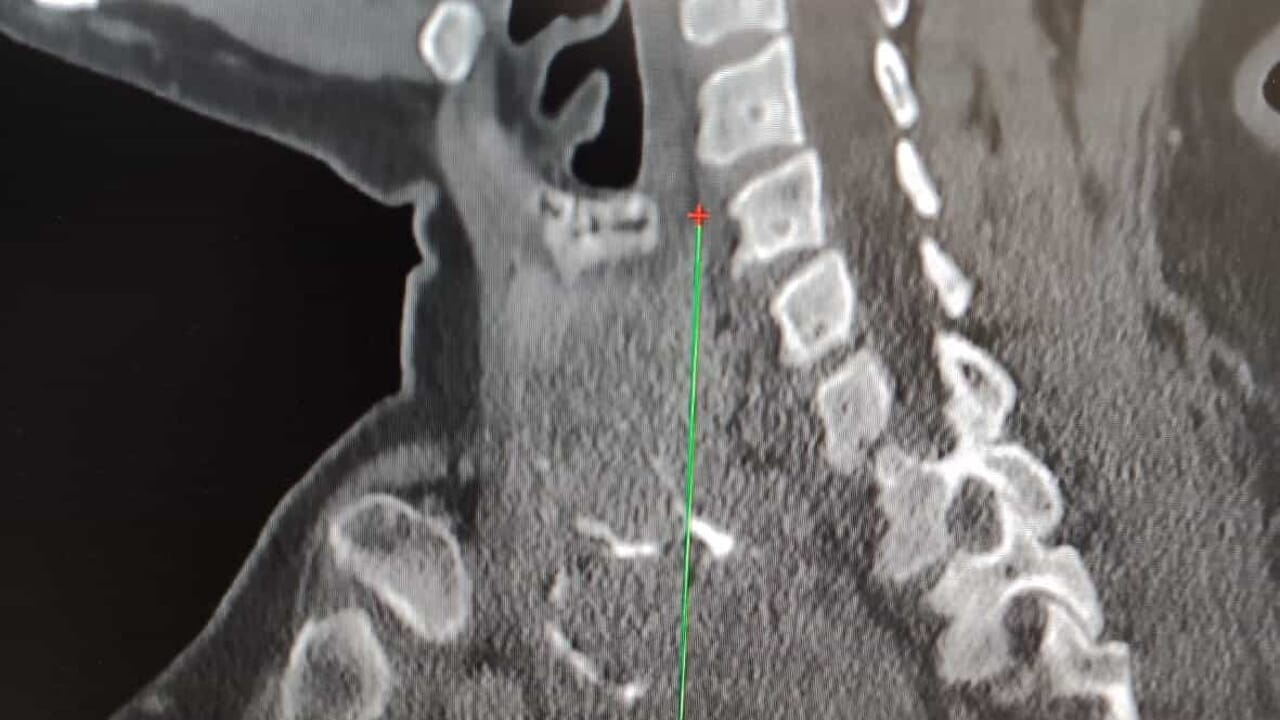

“Gli accertamenti radiologici – spiega il dottor Luigi Madami, otorinolaringoiatra che ha eseguito l’intervento nell’Unità operativa diretta dal professor Nicola Quaranta – hanno mostrato che la tiroide era ingrandita, con un’estensione di circa sette centimetri, si estendeva nel mediastino (la parte alta del torace) e spingeva la trachea verso sinistra, pur lasciandola libera nel passaggio dell’aria. Erano presenti anche piccoli noduli e calcificazioni. L’intervento di rimozione della tiroide (tiroidectomia) è stato eseguito con un approccio sternotomico, cioè aprendo parzialmente lo sterno grazie alla collaborazione multidisciplinare con i cardiochirurghi”.